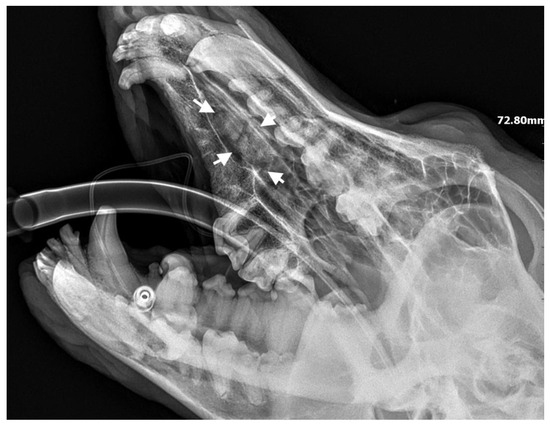

A 7-month-old male Rottweiler was referred for consultation because of severe swelling on the left side of the jaw, with a suspected jaw tumor. Clinical examination revealed no abnormalities in the aforementioned lymph glands and no soreness on palpation. Intraoral examination on the left side revealed severe asymmetry, with enlargement of the facial soft and hard tissues, an absence of permanent teeth, and buccal displacement of deciduous teeth. On the left side, rhinoscopic examination revealed normal anterior nostrils and a left nasal aperture with a lack of patency from the level of the nasal bony inlet to the posterior nostrils. A roentgenogram in the dorsal–ventral projection showed the presence of four ectopic teeth in the maxilla, with the formation of a dentigerous cyst (Figure 2). Using the CLP technique, the ectopic teeth were removed and the cyst walls were lanced. The bone loss caused by the cyst was 7.3 cm × 4.6 cm, and the jawbone left behind was too thin to provide a scaffold for the surrounding tissues and to ensure nasal cavity patency. From a 5 cm pellet of hydroxyapatite polymer material with curdlan previously soaked in saline (according to the manufacturer’s instructions), longitudinal flaps of 5 cm long, 1 cm wide, and 0.1–0.2 cm thick were cut and placed in the bony defect to strengthen the bony scaffolding of the jaw and nasal septum (Figure 3). The gingival flap was sutured with a single suture using 4-0 monofilament material. The first radiological follow-up was performed after 4 weeks, but due to the size of the defect and the size of the pellets of material used, the hydroxyapatite obscured the structures in the nasal cavity, preventing accurate assessment. A rhinoscopic examination revealed patency of the left nasal cavity. It was decided to conduct a radiological follow-up 6 months after the procedure, but the owner, for personal reasons, did not attend the follow-up appointment. After 12 months, another roentgenogram was performed, where a properly healed jawbone with closure of the cyst cavity could be observed. The nasal septum was formed properly, and the resulting bony scaffolding resulted in patency of the left nasal aperture, along with normal airflow on the left side (Figure 4).

Figure 3. Condition after extraction of ectopic teeth. On the left side, a scaffold for the bone formed of hydroxyapatite polymer material is visible (marked with arrows).